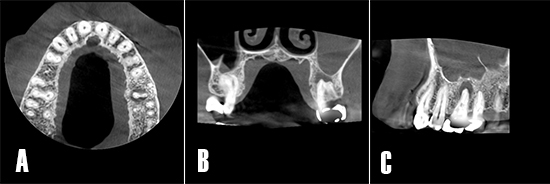

Tras realizar la evaluación radiológica bidimensional, en la ortopantomografía se observa los dientes 2.6 y 2.7 endodonciados y ferulizados mediante prótesis fija cementada (Fig. 2A). La radiografía periapical no evidencia una radiotransparencia bien definida a nivel apical. Las crestas alveolares interproximales se observan íntegras con bordes corticalizados bien definidos (Fig. 2B).

Figura 2. Evaluación radiológica bidimensional. A) La ortopantomografía advierte el tratamiento de conductos a nivel 26 y 27, portadores de prótesis fija metal-cerámica. B) La radiografía periapical muestra los dientes 26 y 27 endodonciados, se observa una imagen radiotransparente poco definida en apical de 26.

La TCHC muestra una imagen osteolítica menos radiodensa que afecta la región apical de 2.6, esta lesión compatible con un proceso osteolítico, es visible en los planos axial, coronal y sagital. Además, se observa cómo el seno maxilar izquierdo, relacionado al diente afectado, se torna más radiodenso y totalmente ocupado (Fig. 3).

Figura 3. Tomografía de haz cónico. A) Corte en el plano axial: se puede observar un área poco radiodensa en la raíz palatina de 26, y advierte la presencia de un proceso osteolítico de origen endodóntico. B) Corte coronal: se observa cómo el patrón de la lesión se extiende en sentido vestíbulo-palatino, además, se aprecia la cavidad sinusal anexa al diente afecto muy radiodensa respecto a su par contralateral. D) Corte sagital: se aprecia la opacificación completa del seno maxilar, la presencia de una septo óseo. La lesión apical tiene una mayor dimensión en la raíz palatina de 26.